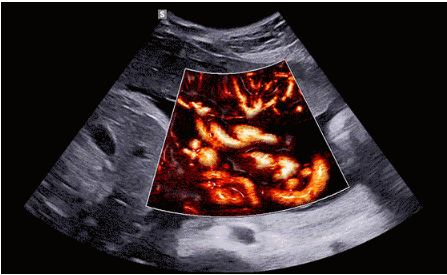

CrystalLive?是三星最新的超聲成像引擎,同時(shí)增強(qiáng)了2D圖像處理能力、3D渲染能力和彩色信號(hào)處理能力,能夠在復(fù)雜情況下提供出色的圖像性能,具備檢測(cè)外周血管、微循環(huán)血流的能力。

3D/4D成像方面,Hera i 10通過結(jié)合先進(jìn)的圖像渲染技術(shù),著重加強(qiáng)了邊緣和小結(jié)構(gòu)的可視化能力。